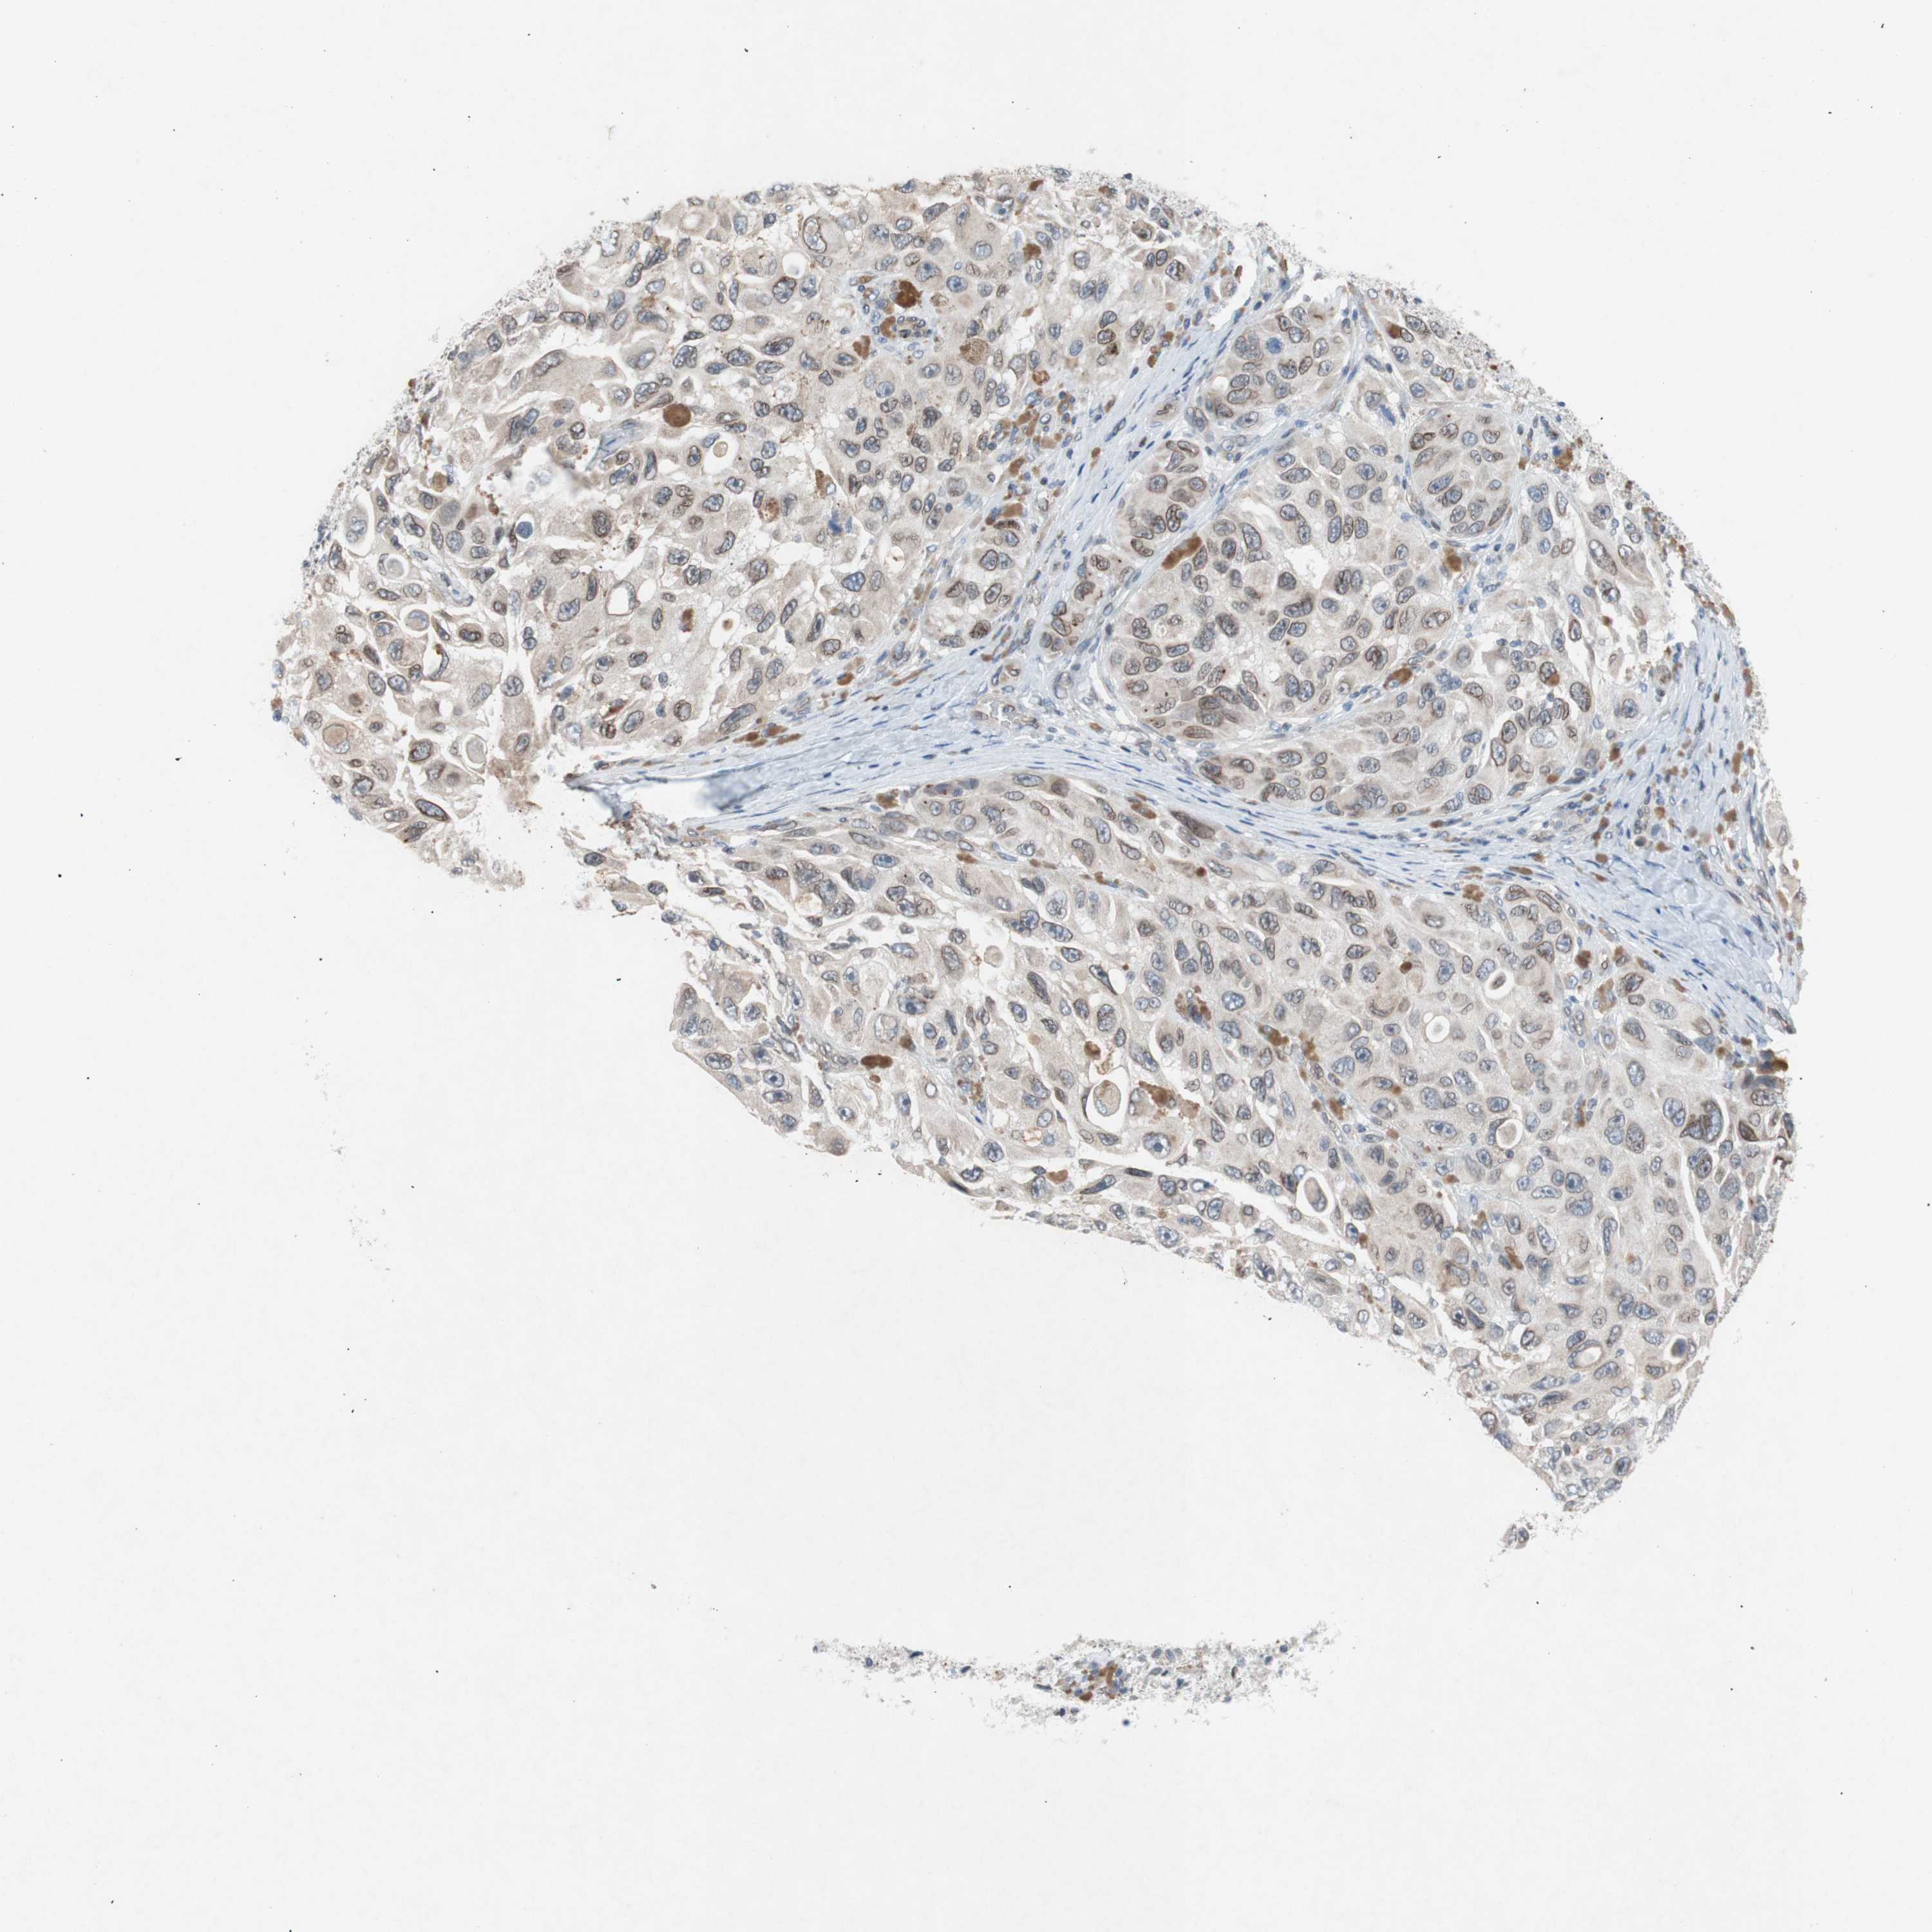

MELANOMA - Protein expressioni

A mouse-over function shows sample information and annotation data. Click on an image to view it in a full screen mode. Samples can be filtered based on level of antibody staining by selecting one or several of the following categories: high, medium, low and not detected. The assay and annotation is described here.

Antibody stainingi

Antibody staining in the annotated cell types in the current human tissue is reported as not detected, low, medium, or high, based on conventional immunohistochemistry profiling in selected tissues. This score is based on the combination of the staining intensity and fraction of stained cells.

Each image is clickable and will lead to virtual microscopy that enables deeper exploration of all samples and also displays staining intensity scores, fraction scores and subcellular localization as well as patient and tissue information for each sample.

Antibody HPA001056

Antibody CAB005081

Staining

High

Medium

Low

Not detected

Intensity

Strong

Moderate

Weak

Negative

Quantity

>75%

75%-25%

<25%

None

Location

Nuclear

Cytoplasmic/membranous

Cytoplasmic/membranous,nuclear

Malignant melanoma, NOS

Malignant melanoma, Metastatic site